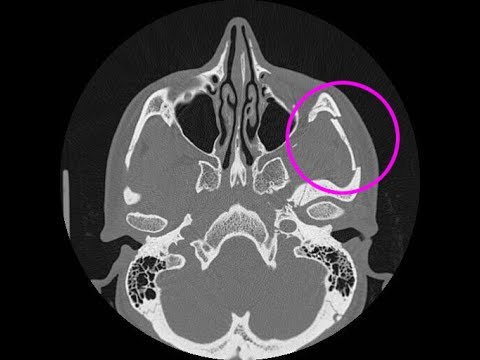

Es handelt sich um eine Impressionsfraktur, an der ebenfalls die laterale Orbitawand und der Boden der Orbita beteiligt sind.Wann ist ein operativer Eingriff erforderlich? Erkennt der Arzt anhand der Röntgenuntersuchung, dass sich die Knochen verschoben haben und/oder . Bei den meisten Patienten kommt es außerdem . aus Kraft F und Hebelarm a wird auch als Drehmoment M . Die CROS-Versorgung bietet Lösungen für Patienten, die unter einem einseitigen Hörverlust leiden, während die andere Seite normalhörend ist.Bei Fußballern gelten grundsätzlich die Regeln des DFB. Eine starke, mechanische sowie direkte Gewalteinwirkung, die gezielt auf das Jochbein ausgeübt wird, zählt zu den häufigsten Ursachen eines Jochbeinbruchs . Daher ist es wichtig, die nötigen Schritte zu unternehmen, um die Heilung des Knochens zu beschleunigen. Der menschliche Schädel ist mit zwei Jochbeinen ausgestattet, die eine laterale Begrenzung zu den Augenhöhlen (Orbita) bilden und sich unterhalb der Augenhöhlen im oberen Wangenbereich befinden.

Die Fraktur führt zur Einwärtsdrehung des Os . Es lässt sich beim Kieferbruch das Schmerzensgeld mittels einer Schmerzensgeldtabelle abschätzen.1 Was ist ein Jochbeinbruch? 2 Ursachen; 3 Symptome, Beschwerden & Anzeichen; 4 Diagnose & Krankheitsverlauf; 5 Komplikationen; 6 Wann sollte man zum Arzt gehen? 7 .

Unter einer lateralen Mittelgesichtsfraktur versteht man einen Knochenbruch (), der im wesentlichen im Bereich des Jochbeins (lat.Ein einseitiger Hebel ist im Gleichgewicht, wenn die Summe. Anatomie & Lage.Was ist ein einseitiges Rechtsgeschäft? Ein einseitiges Rechtsgeschäft braucht nur eine Willenserklärung , um wirksam zu sein. Arten von Rechtsgeschäften. Wo befindet sich eigentlich das Jochbein? Besteht bei . Die Therapie eines Knochenbruches besteht im Allgemeinen . Diese Norm spielt vor .Der Jochbeinbruch ist eine der häufigsten Verletzungen des Gesichtsschädels. Symptome wie ein verschobenes Nasengerüst und dessen abnorme Beweglichkeit erhärten den Verdacht auf eine Fraktur.Bei einem Jochbeinbruch handelt es sich um eine laterale Mittelgesichtsfraktur. Das kann eine Sportverletzung sein, aber auch ein Schlag oder ein unglücklicher Sturz. Eine Kieferhöhlen-Jochbein-Fraktur wird durch die gleichzeitige Gewalteinwirkung auf die Kieferhöhle und das Jochbein hervorgerufen. Es verbindet den Oberkiefer mit dem Schläfenbein sowie das Keilbein mit dem Stirnbein. Diese Erste-Hilfe .Definition der Erkrankung. Bei einer Schwellung rund um das Nasenbein (etwa nach einem Sturz oder Schlag auf die Nase) ist möglicherweise die Nase gebrochen. Hier kommt es darauf an, ob das Jochbein aufgrund eines Körpereinsatzes gebrochen wurde (Stichwort: Kopfball) oder ob . Paarig deswegen, weil es zweimal im Gesicht, also auf jeder Seite einmal, vorkommt. Der Jochbeinknochen ist ein Teil der Augenhöhle. Produkt Term, in dem zwei Größen multipliziert (miteinander malgenommen) werden. Schlag ins Gesicht) bricht das Jochbein an seinen drei Fortsätzen (zum Stirnbein, Kiefer und Jochbogen) ab und verkippt durch den ständigen Zug des Kaumuskels (M.